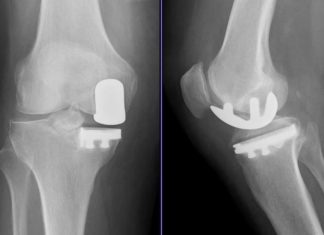

„Im rechten Knie hatte ich gar keinen Knorpel mehr, links war mehr als die Hälfte weg“, erzählt sie. Der Knorpel dient als Stoßdämpfer zwischen den Knochen. Ist er abgenutzt, sind viele Bewegungen schmerzhaft. Monika Krampfl entschied sich, gleich beide Kniegelenke in einer OP durch Totalendoprothesen ersetzen zu lassen. Eine Zweitmeinung von einem anderen Arzt holte sie sich für diesen großen Eingriff nicht ein, aber sie bereut es auch nicht. „Ich habe blindes Vertrauen zu Prof. Beckmann“, sagt sie. Rund um die Operation sei dann auch alles sehr gut gelaufen. Nervös oder ängstlich sei sie zu keinem Zeitpunkt gewesen.

In der Reha-Einrichtung konnten die Teilnehmer auch eine Motorschiene benutzen. Der Vorteil der Schiene ist, dass sie das Bein und das Knie automatisch bewegt und die Patienten sich nicht selbst anstrengen müssen. Durch das Training mit der Schiene und weiteren Übungseinheiten wird der Bewegungsradius des Knies mit der Zeit immer größer.

Die Anzahl der Schienen, die zwischen 4.000 und 6.000 Euro kosten, war in der Reha-Einrichtung jedoch begrenzt. Die Schiene kann auch vom Arzt verschrieben und für eine bestimmte Zeit zu Hause genutzt werden. Monika Krampfl nutzte diese Möglichkeit und trainierte alleine weiter. „Ich habe mit 70 Grad Beugung angefangen“, sagt sie. „Als ich die Schiene nach sechs Wochen wieder abgegeben habe, war ich bei 100 Grad.“